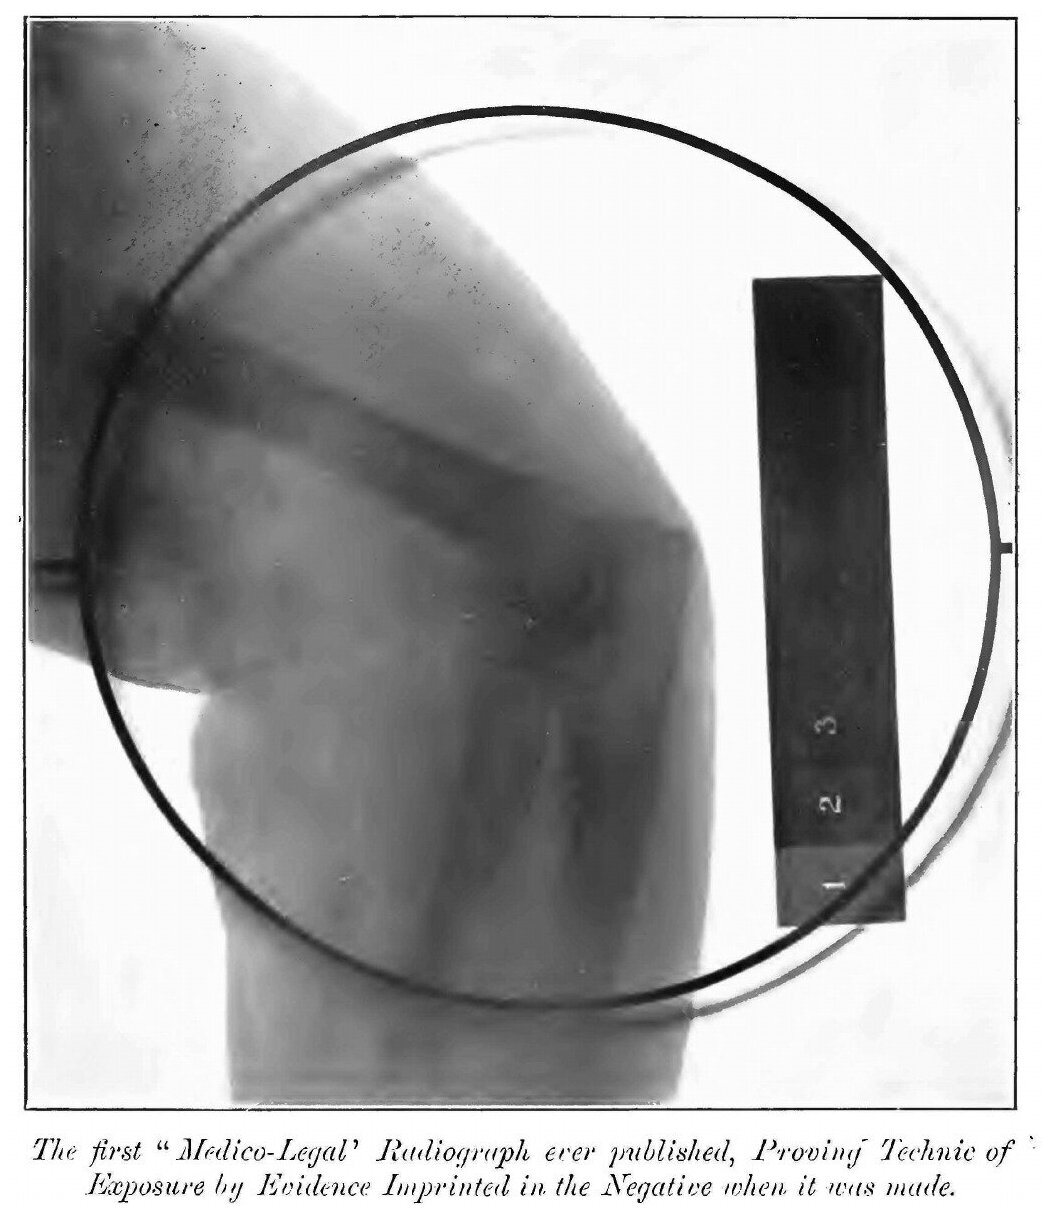

Эта книга - репринт оригинального издания (издательство "New York : E.R. Pelton", 1902 год), созданный на основе электронной копии высокого разрешения, которую очистили и обработали вручную, сохранив структуру и орфографию оригинального издания. Редкие, забытые и малоизвестные книги, изданные с петровских времен до наших дней, вновь доступны в виде печатных книг.A system of instruction in X-ray methods and medical uses of light, hot-air, vibration and high-frequency currents : a pictorial system of teaching by clinical instruction plates with explanatory textИздательство Нобель ПрессМягкий переплетОбъем - 498 стр.Формат - 210x280 мм.ISBN 978-5-8822-9404-4Год издания: 2012